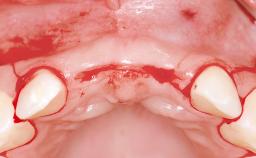

Replacement of Four Incisors with a Fixed Partial Denture on Two Narrow-Neck Implants after Implant Failure

| Soft Tissue Anatomy | Intact | Defective | |

| Bone Volume | Horizontally and vertically sufficient | Horizontally deficient | Deficient vertically or deficient vertically AND horizontally |